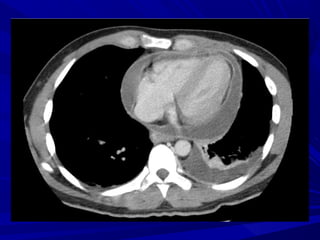

CT, MRICT, MRI

Thickness of the pericardiumThickness of the pericardium

CalcificationsCalcifications

Atrial dilatationAtrial dilatation

SVC, IVC distensionSVC, IVC distension

Ascites, pleural effusionAscites, pleural effusion

absence of pericardial thickening arguesabsence of pericardial thickening argues

against the diagnosis of constrictionagainst the diagnosis of constriction